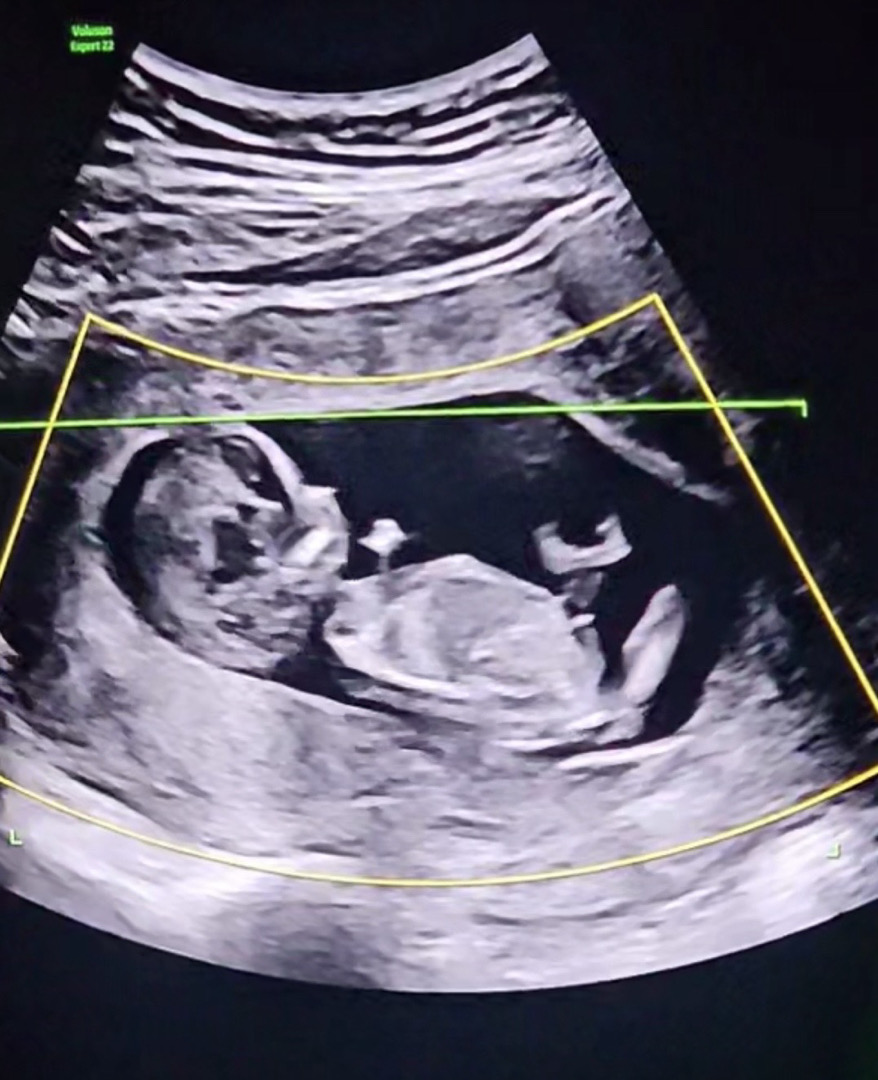

12주 4일차 성별 투표 뷰탁드려용❣️ 저기 보이는게 맞다면..👶🏻😂